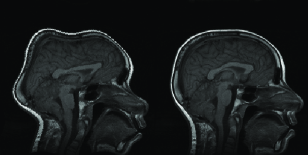

Images in the first row of Figure 4 shows a source and target images in image scale. In the second row on the same figure, the same slices are displayed after standardization using the parameters defined above.